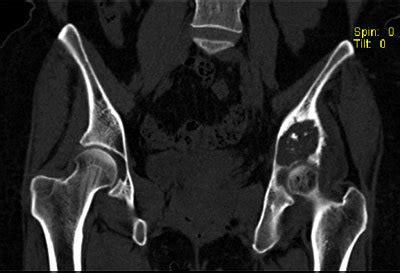

Bone cancers are rare, and usually, they affect children than adults. Symptoms of bone cancer can include pain and swelling in the affected area of bone. Bone pain can cause a dull or deep ache in a bone or bone region (e.g., back, pelvis, legs, ribs, arms). Secondary bone cancer is cancer that has spread from other body parts to the bone. This gradually progresses to a persistent ache or an ache that comes and goes, which.

Table showing the symptoms of cervical, ovarian, uterine, vaginal, and vulvar cancers. It checks your reproductive organs (see picture below) for. Early stage vaginal cancer and precancerous lesions do not tend to cause noticeable symptoms. Primary bone cancer means that the cancer starts in a bone. Bone pain can cause a dull or deep ache in a bone or bone region (e.g., back, pelvis, legs, ribs, arms). Unexplained, persistent pelvic and/or back pain. Abnormal vaginal bleeding or discharge is common on all gynecologic cancers except vulvar cancer. In pelvic bone cancer, when the size of the tumor increases it puts enormous amounts of pressure upon the bones. Your treatment will depend on several things including how far it's. Bone cancer can begin in any bone in the body, but it most commonly affects the pelvis or the long bones in the arms and legs. Several different kinds of tumors can grow in bones: Possible symptoms of bone cancer include: The appearance of a malignant tumor is characterized bymore aggressive course, so the clinical picture here is more pronounced.

Bone Cancer|Types|Stages|Causes|Symptoms|Treatment-Surgery ... from www.epainassist.com In pelvic bone cancer, when the size of the tumor increases it puts enormous amounts of pressure upon the bones. Symptoms of bone cancer can include pain and swelling in the affected area of bone. Surgical removal is the most common treatment, but chemotherapy and radiation. Learn more about the symptoms, risk factors, diagnosis, types, treatment, and outlook for bone cancer. Some people with bone cancer have no symptoms other than feeling a painless lump. Some people experience other symptoms as well. Bone cancer can begin in any bone in the body, but it most commonly affects the pelvis or the long bones in the arms and legs. Unexplained, persistent pelvic and/or back pain.